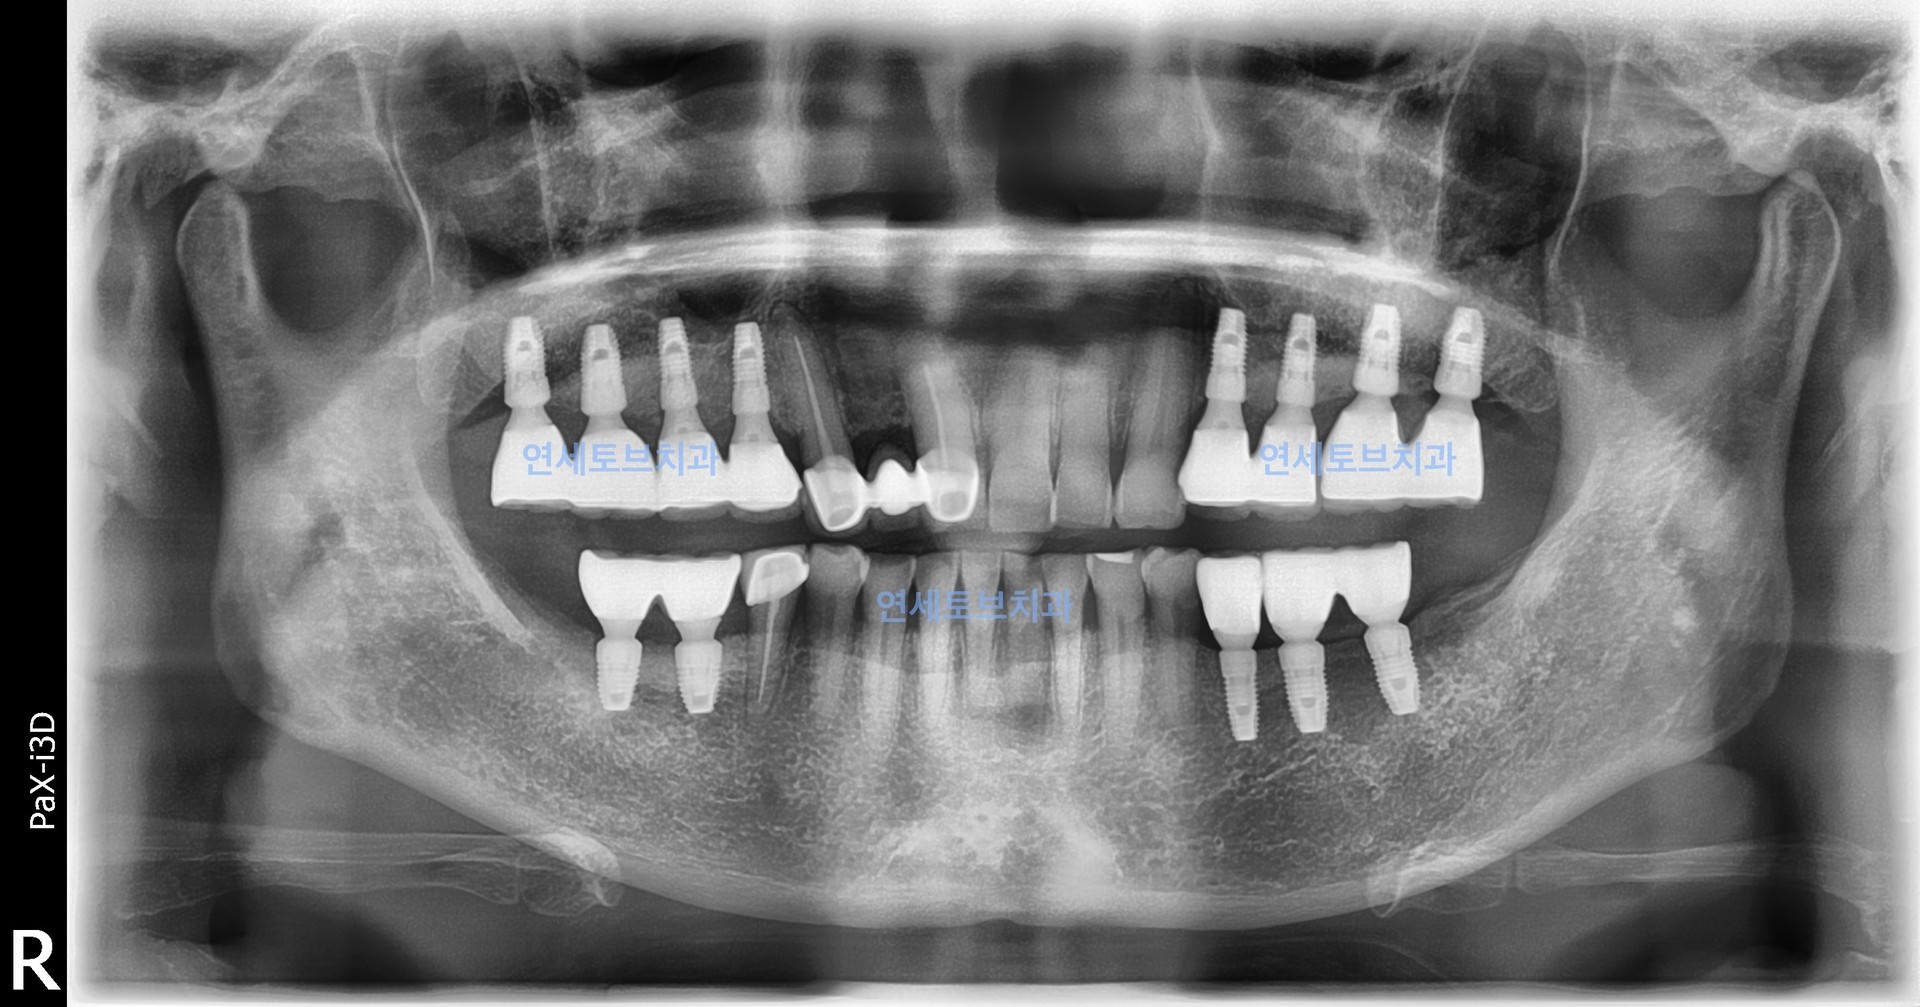

#2

상악동 골이식술은 상악 어금니 부위 임플란트 식립에 필수적인 뼈를 확보하는 신뢰도 높은 술식으로, 치조골이 부족한 환자에게 임플란트의 성공률을 높여주는 중요한 수술입니다